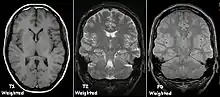

Each tissue returns to its equilibrium state after excitation by the independent relaxation processes of T1 (spin-lattice; that is, magnetization in the same direction as the static magnetic field) and T2 (spin-spin; transverse to the static magnetic field). To create a T1-weighted image, magnetization is allowed to recover before measuring the MR signal by changing the repetition time (TR). This image weighting is useful for assessing the cerebral cortex, identifying fatty tissue, characterizing focal liver lesions, and in general, obtaining morphological information, as well as for post-contrast imaging. To create a T2-weighted image, magnetization is allowed to decay before measuring the MR signal by changing the echo time (TE). This image weighting is useful for detecting edema and inflammation, revealing white matter lesions, and assessing zonal anatomy in the prostate and uterus.

The standard display of MR images is to represent fluid characteristics in black-and-white images, where different tissues turn out as follows:

| Signal | T1-weighted | T2-weighted |

| Intermediate | Gray matter darker than white matter[23] | White matter darker than grey matter[23] |